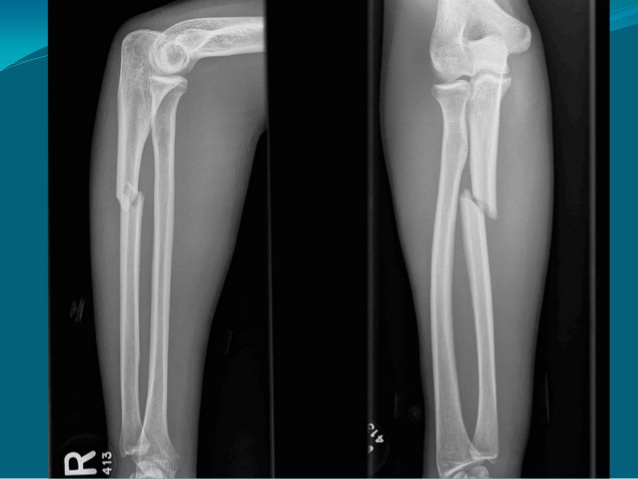

Hỏi bệnh sử và khám thực thể. Chụp X-quang cẳng tay để phát hiện xương gãy.

Điều trị phụ thuộc vào vị trí của tổn thương, mức độ nghiêm trọng của các vết nứt và độ tuổi của bệnh nhân. Chăm sóc không phẫu thuật bao gồm cố định với nẹp hoặc bó bột cố định. Trường hợp nặng hơn cần phẫu thuật nhằm mục đích nắn lại chính xác và dùng dụng cụ như: đinh, nẹp, vít để cố định xương gãy.